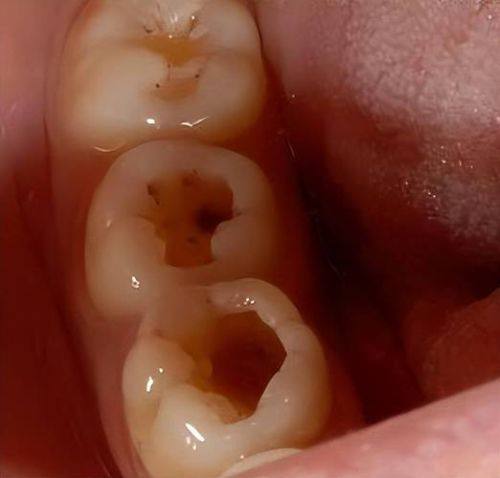

龋洞大小、部位

龋洞的大小和部位对补牙成效的维持也有重要影响。如果龋洞较小,补牙时对牙齿的损伤相对较小,填充材料与牙齿的结合也会更紧密,补牙成效就更持久。相反,如果龋洞较大,牙齿的结构已经受到重度破坏,即使补好牙,也可能因为牙齿本身的稳定性较差,导致补牙材料容易脱落,从而缩短补牙成效的维持时间。此外,龋洞的部位也特别关键,如果龋洞位于牙齿的咬合面等容易受力的部位,补牙材料受到的压力较大,就更容易出现磨损和脱落的情况。